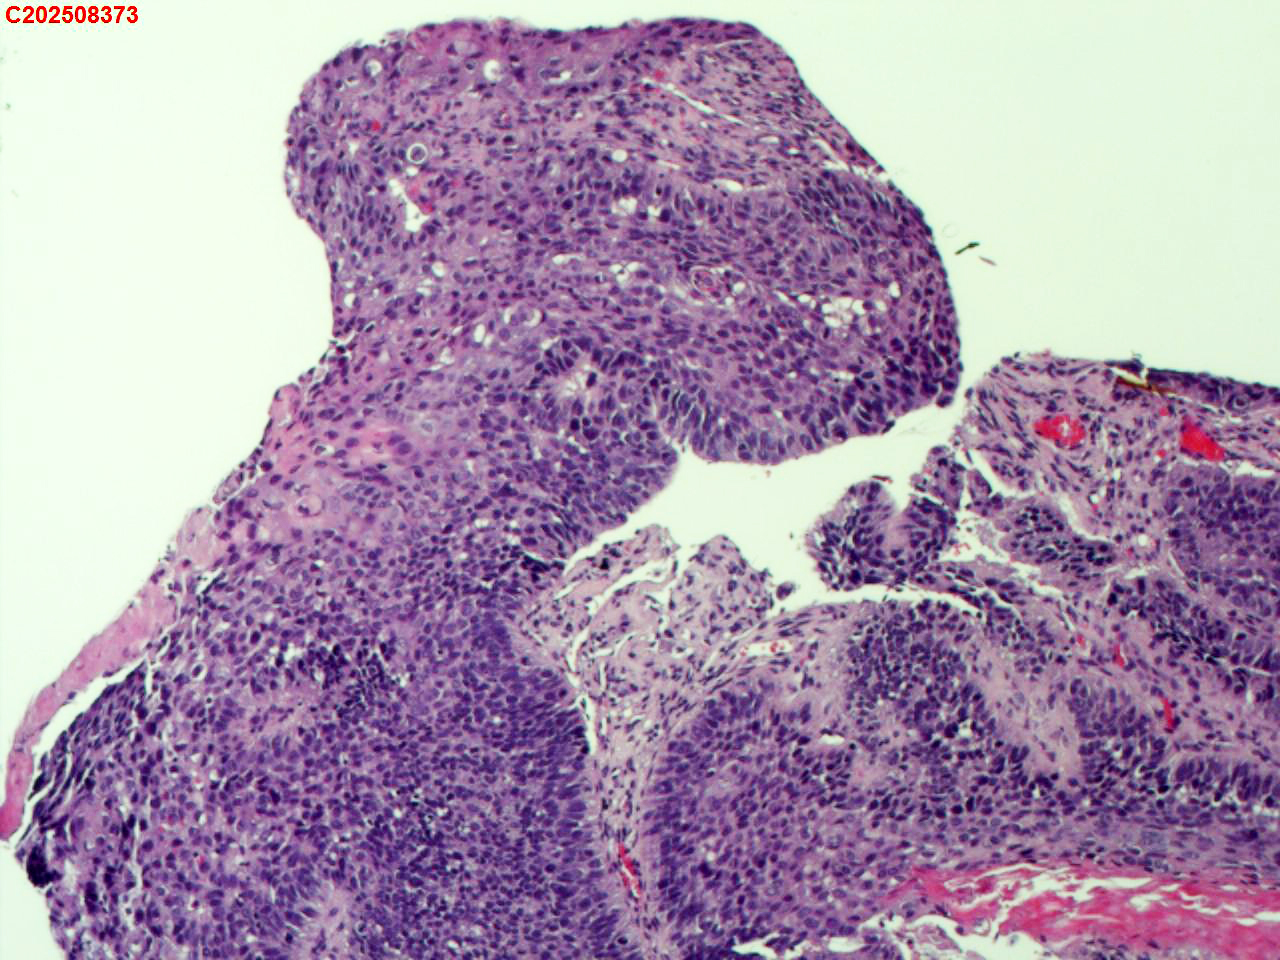

纤支镜咬检

性别

男

年龄

40岁

临床诊断

肺癌?

一般病史

增强CT提示右肺中叶粘液栓;气管镜见右肺中叶外侧段新生物,考虑恶性可能。

标本名称

大体所见

图1

鳞状细胞癌